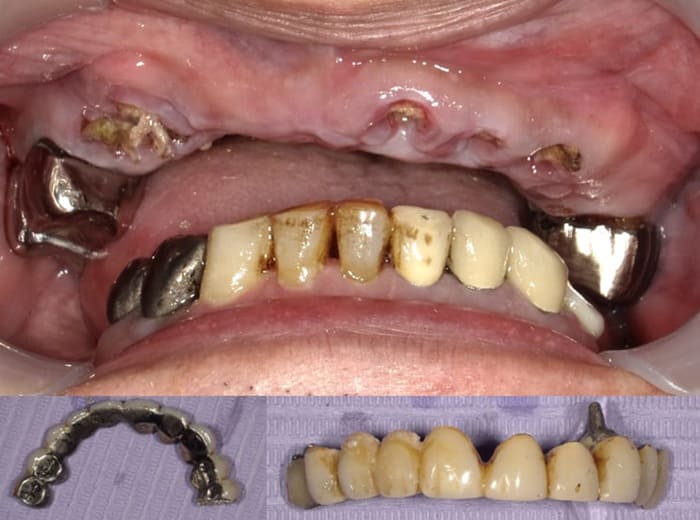

Case.01(40歳代 女性)

臼歯の Vertical stop の獲得と前歯の咬合・審美の改善のための治療を行った症例

歯科恐怖症で歯科医院に受診できずに奥歯がどんどん崩壊して噛むことができず前歯も割れたので全顎的な治療を希望して来院。

Case.02(70歳代 男性)

20年ほど前に入れた第2小臼歯から反対側の第2小臼歯まで8本の歯をつないでいたブリッジが取れて噛めなくなり全顎的な治療を希望して来院

上顎前歯を含む第2小臼歯から対側の第2小臼歯までの10本のブリッジが脱離しそれを支えていた歯自体が保存できない状態であった。また下顎の臼歯部も欠損しており、このことで垂直的な咬合の安定が得られず前歯に負担がかかる崩壊脱離したと考えられる。